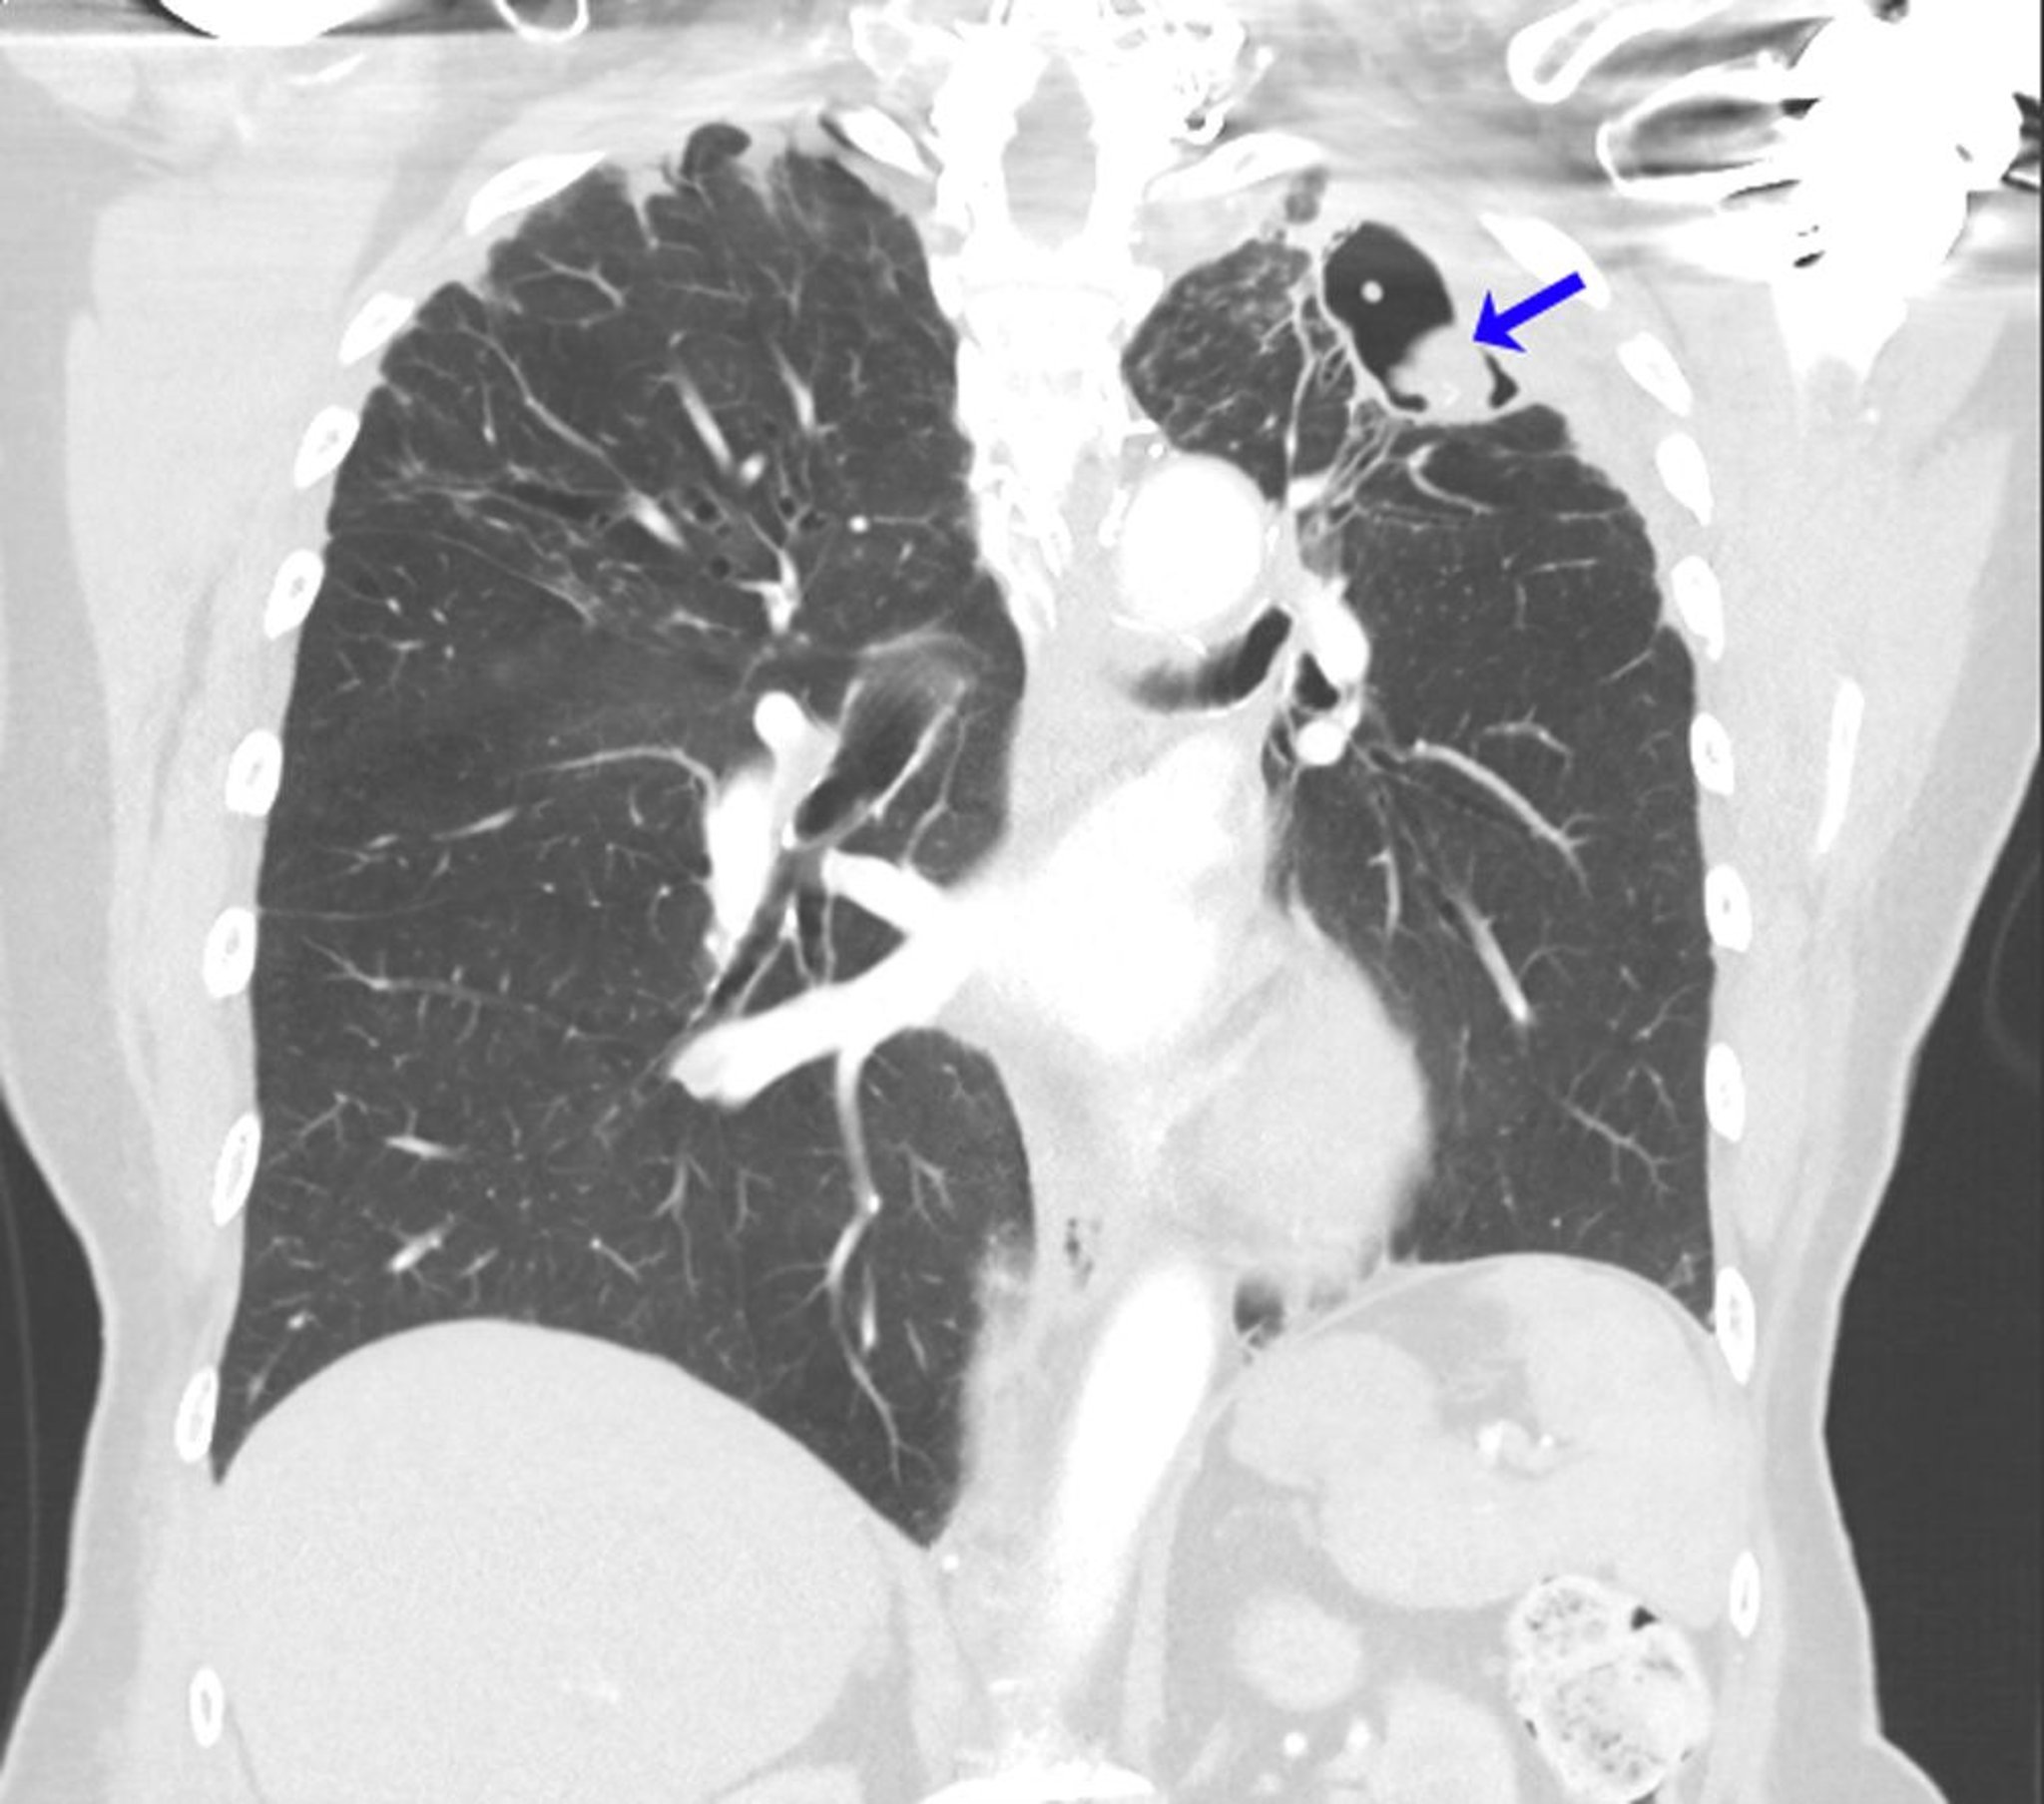

Recurrent Aspergilloma

This CT scan shows the lungs of a person with a history of allergic bronchopulmonary aspergillosis in the setting of asthma. After left upper lobectomy for aspergilloma, recurrent mycetoma developed at the left lung apex (arrow).

Image courtesy of Paschalis Vergidis, MD, MSc.